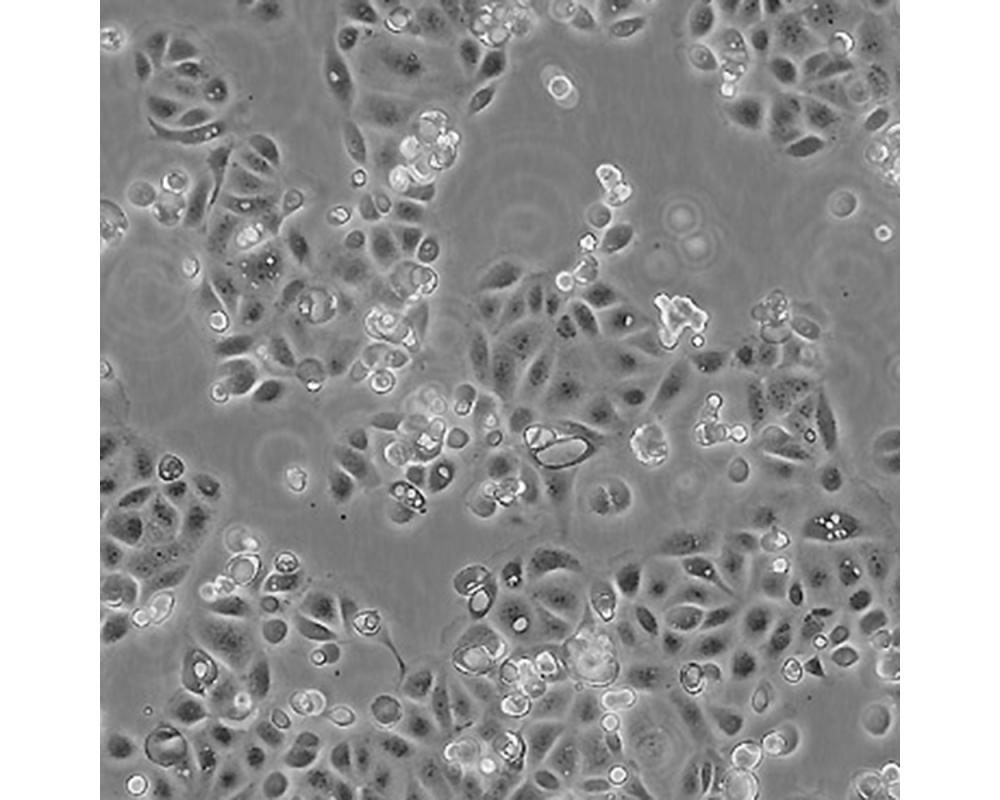

SW1990

中文名稱 人胰腺癌細胞

組織來源 胰腺癌;男性

生長特性 貼壁

培養(yǎng)基 L15,90%;FBS,10%;雙抗。

培養(yǎng)條件 Atmosphere: Air, 95%; CO2, 5%。Temperature: 37℃